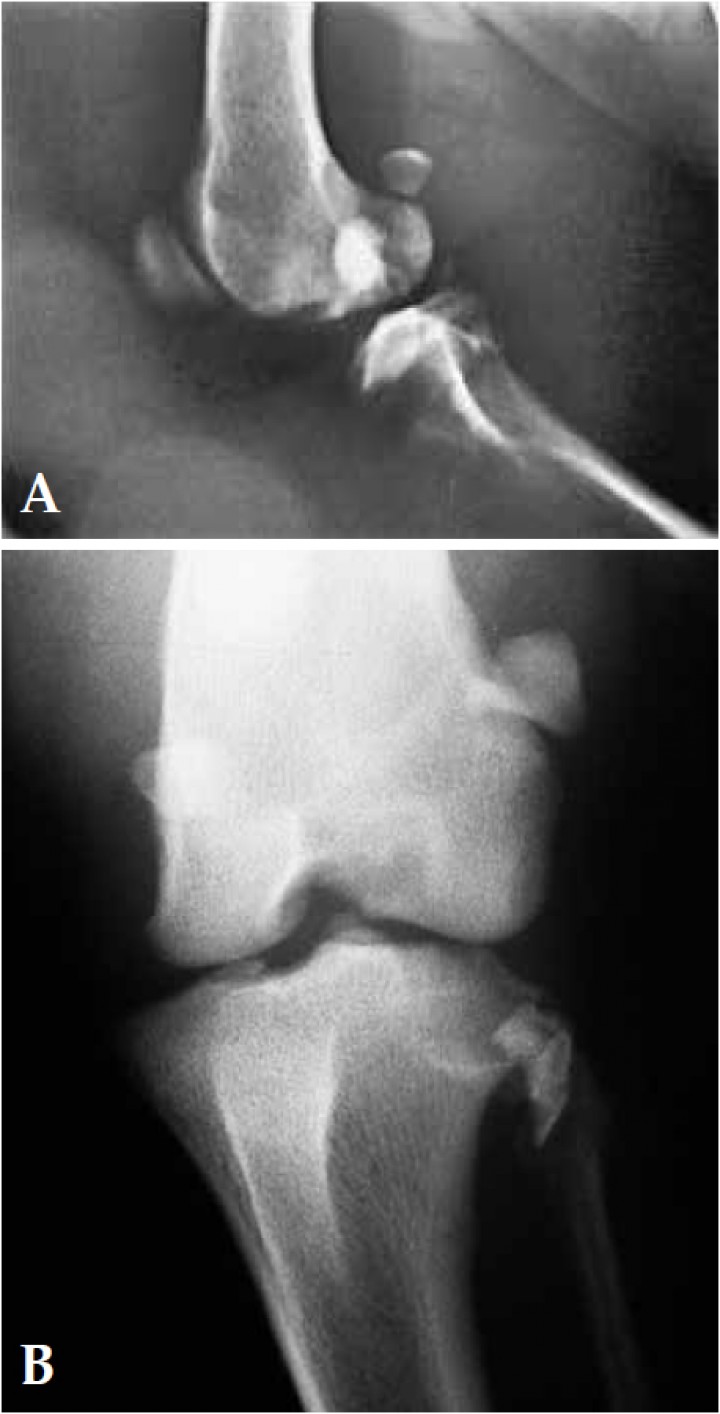

La exploración física de la rodilla izquierda evidenció prueba de cajón anterior, y de compresión tibial y valgo tibial, positivas. Las radiografías ortogonales (lateral y postero-anterior) muestran subluxación articular y un pequeño fragmento óseo, desplazado lateralmente, procedente de una fractura en el área medial del surco del tendón del músculo extensor digital largo de la cara lateral de la epífisis proximal de la tibia izquierda (Fig. 1A), pudiéndose apreciar mejor este detalle en la vista posterior-anterior (Fig. 1B).

<p>A. Radiografía lateral y B. Radiografía posteroanterior de la articulación de la rodilla izquierda en el momento de la presentación. Se observa una subluxación articular y un pequeño fragmento óseo desplazado lateralmente procedente de una fractura en el área medial del surco del tendón del músculo extensor digital largo de la cara lateral de la epífisis proximal de la tibia izquierda.</p>

Figura 1

A. Radiografía lateral y B. Radiografía posteroanterior de la articulación de la rodilla izquierda en el momento de la presentación. Se observa una subluxación articular y un pequeño fragmento óseo desplazado lateralmente procedente de una fractura en el área medial del surco del tendón del músculo extensor digital largo de la cara lateral de la epífisis proximal de la tibia izquierda.